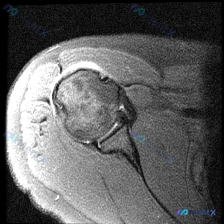

看到一份肩部MRI的病例资料,用户提到观察到"盂唇病变",但影像报告显示冈上肌腱全层撕裂伴滑囊积液,关节软骨与盂唇尚完整。大家觉得这个病例更倾向于什么诊断?是单纯的肩袖撕裂,还是合并盂唇病变?欢迎讨论。

整理了一份肩部影像病例资料,核心情况如下: 1. 影像资料:肩部MRI T1加权冠状位序列 2. 核心疑问:临床怀疑盂唇病变,该序列影像下能观察到什么? 3. 初步影像所见:当前序列显示肱骨头、肩峰、冈上肌腱等结构大致完整,上方盂唇形态及信号未见明显异常,未见明确肩袖撕裂、骨性撞击征象。 想和大家讨...

最近看到一份单一T1加权冠状位肩关节MRI影像,想评估是否存在盂唇病变。但了解到MRI诊断肩关节病变往往需要多序列联合判断,仅凭T1序列有一定局限性。大家怎么看这个影像的诊断价值?

最近看到一个肩部MRI病例,资料里只有T1序列冠状位影像。影像分析显示:肱骨头、肩胛盂形态正常,冈上肌腱走行连续无撕裂,上方盂唇呈三角形低信号、轮廓规则,未见明显的信号异常或撕裂征象。 虽然影像没找到盂唇的结构性病变,但患者很可能有持续性肩痛症状(不然也不会做MRI)。大家第一眼看到这种情况,会先往...